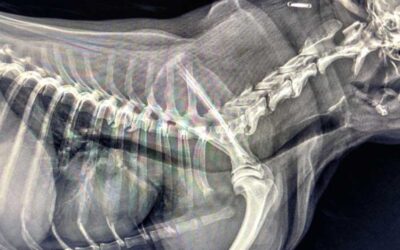

Zapadanie tchawicy u psów (TCS-Tracheal Collapse Syndrome)

Źródło: https://wetgliwice.pl/ Zapadanie tchawicy u psów (TCS-Tracheal Collapse Syndrome) Zapadanie tchawicy u psów (TCS-Tracheal Collapse Syndrome) jest przewlekłą chorobą …